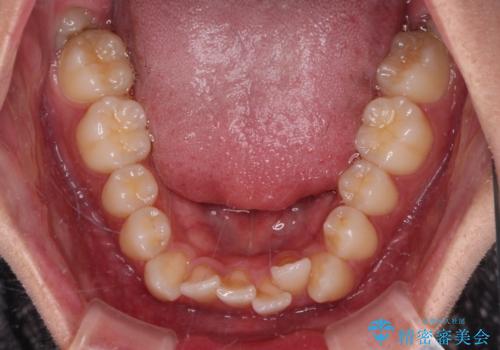

- 八重歯と口元の閉じにくさを気にして来院された患者様です。

非抜歯矯正で歯列を整えると、治療後に口元が今よりも突出する可能性が高かったため、上下左右の第一小臼歯4本を抜歯し、ワイヤー装置にて矯正治療を行うこととしました。

患者様の望んでいた通りの歯列や口元に仕上げることができました。